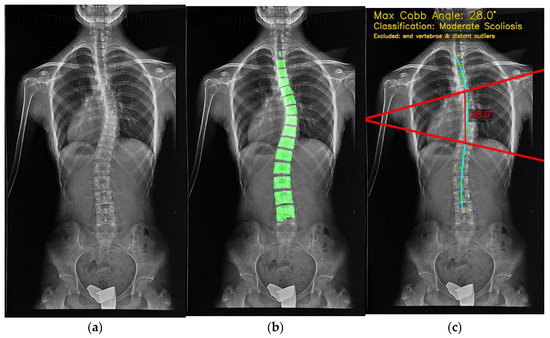

The results are presented to the user through a comprehensive visualization interface, as shown in Figure 12. Here, the maximum CA, scoliosis classification, and anatomical overlays are superimposed on the original radiograph, highlighting the analyzed vertebrae, endplate lines, and curvature trajectory. This graphical representation ensures interpretability, reproducibility, and clinical trust. When the analysis finishes, the “Maximum CA” (28.0°) is shown with key details for clinical decisions. The bottom row lists the measured vertebral range (Spine #5–#10). Red lines and blue reference points on the X-ray illustrate how the angle is computed. “Download Visualization” lets users export the figure, and “Perform New Image Analysis” restarts the workflow. Switching to the segmentation tab overlays a transparent green vertebral mask on the X-ray (Figure 13), showing extracted vertebrae and boundaries. The translucency lets users assess tissue and contours together. “Download Segmentation” saves/exports the mask for further analysis or reporting.

Figure 12.

CA calculation results: Visual overlay of vertebral endplates and classification.

The input X-ray image (a), vertebra segmentation (b) and final CA calculation output (c).

In Figure 12 and Figure 13, all colours and symbols follow a consistent convention. The bright green regions indicate the vertebral segmentation mask predicted by the U-Net model. The cyan spinal curve with small markers represents the fitted midline obtained from the centroids of the segmented vertebrae and is used for automatic curve detection. The solid red lines correspond to the upper and lower endplate tangents defining the maximum Cobb angle, and the red numeric label (e.g., “28.0°”) reports this Cobb angle in degrees. The yellow text at the top of the panel summarises the maximum Cobb angle and the corresponding scoliosis category (e.g., “Moderate Scoliosis”). The subfigure labels (a), (b) and (c) refer, respectively, to the original X-ray image, the vertebra segmentation overlay, and the final Cobb-angle visualisation generated by SpineCheck-AI. Interface text such as “Curve 1: 28.0° (Spine #5–#10)” denotes the first detected curve and the index range of vertebrae along the automatically identified spinal sequence.